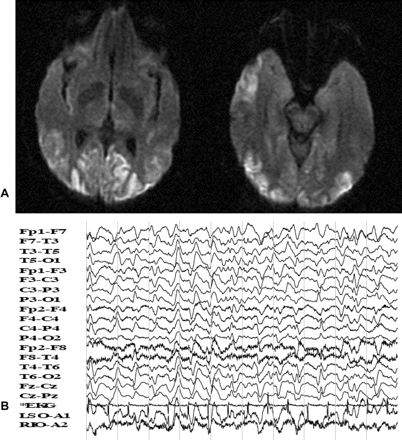

一位51岁女性因快速进行性记忆丧失、语言障碍和困难进行例行的日常活动。在入学之前,她在精神病院,因为视觉幻觉和异常行为。她患失语症,皮质盲和痉挛性夸张的反应,双边巴宾斯基,和频繁的多焦点的肌肉阵挛性抽搐。CSF 14-3-3蛋白升高。病人死后4个月的进展。这个病人可能的零星的克雅氏病(CJD), Heidenhain变体。1视觉障碍和迅速发展的主要症状被称为“Heidenhain变体”自1954年以来,库贾氏症。它展示了最为明显neuropathologic /放射枕叶的变化(图)。